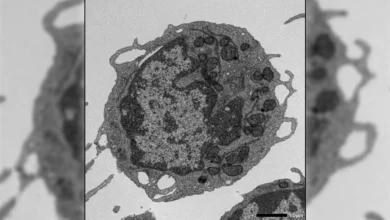

UCLA Scientists Uncover "Zombie" Immune Cells Driving Aging and Fatty Liver Disease, Paving Way for Novel Therapeutic Strategies

UCLA scientists have made a significant breakthrough, identifying a previously overlooked yet highly detrimental group of immune cells that stealthily…